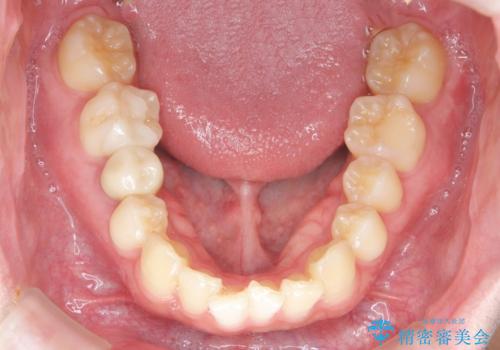

前歯のがたつきをなおしたい マウスピース矯正

- 気になる前歯のがたつきをきれいにしたい。と矯正治療を希望され来院されました。

大きな歯列の乱れはないため、倒れ込んでいる奥歯の傾きの改善、前歯のがたつきを改善する治療を計画します。

見た目が良くなっただけではなく、歯ブラシがしやすくなった!と治療後の歯並びに喜んでいただくことができました。